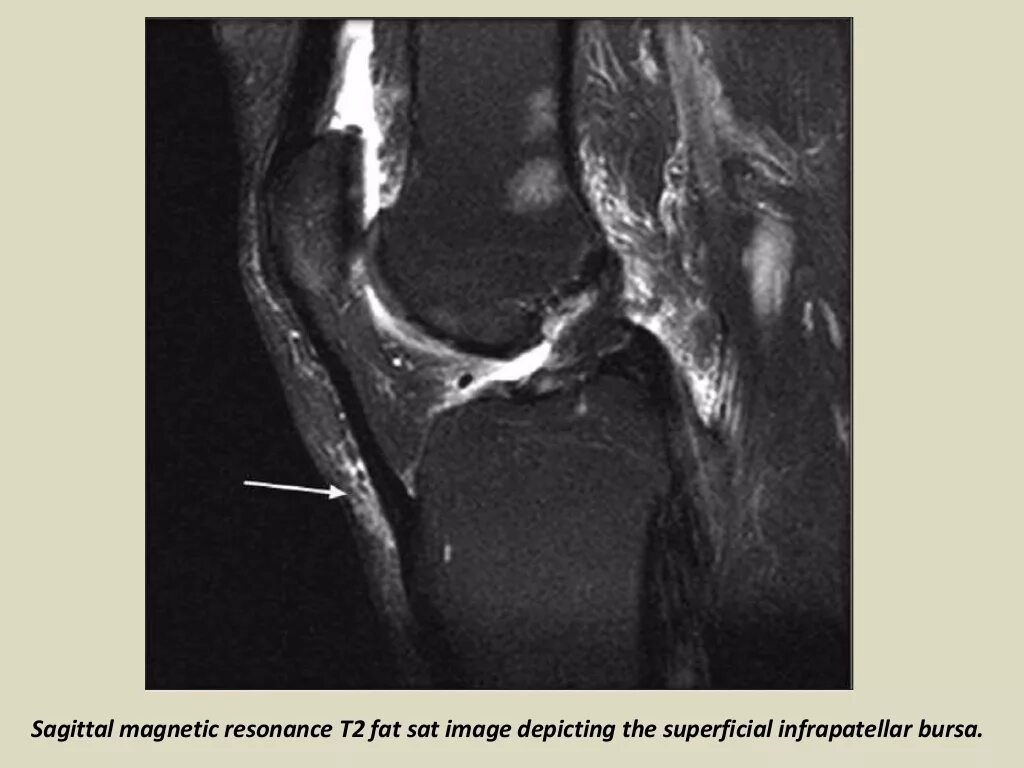

Что такое синовит коленного сустава на мрт